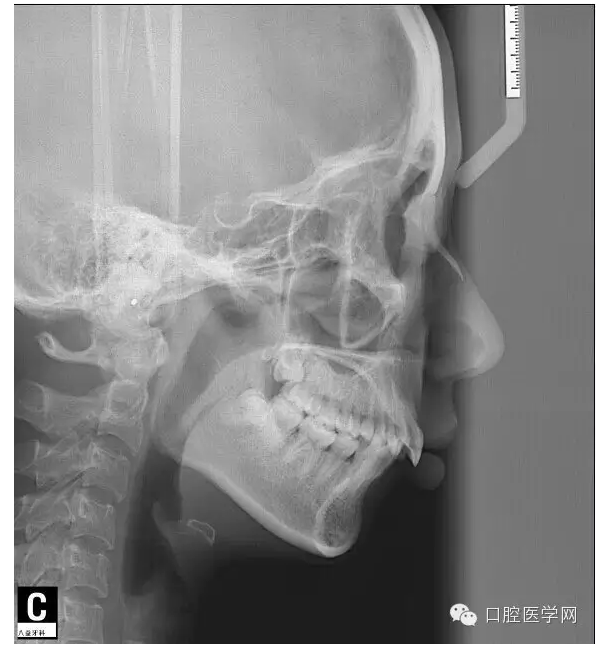

這是一位我同事接診的一位患者,成年女性,安氏II類,高角,下頜后縮,重度深覆合,上下中線右偏,原本做過(guò)一次矯正,4個(gè)4已經(jīng)拔除。

這個(gè)患者,II類高角,下頜后縮,所以我們不能抬高磨牙,另外兩個(gè)上頜中切牙牙根短小,也不能大幅壓入。